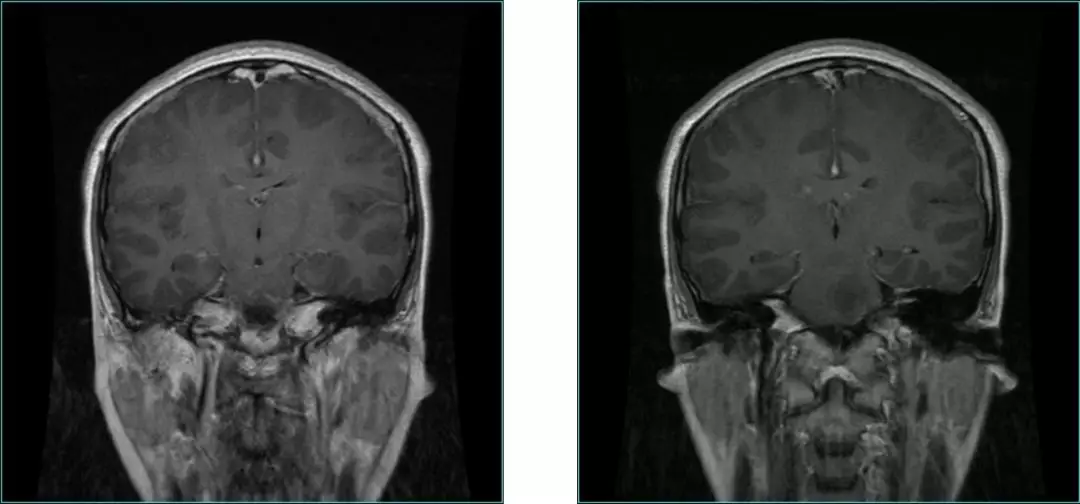

Pre-op MRI Contrast

Post-op MRI with contrast

Post-op MRI